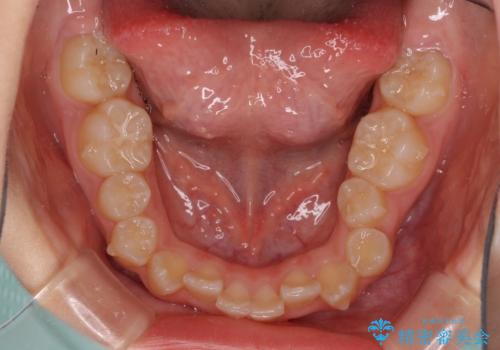

- 小児矯正の頃から診察を行っている患者様です。

上顎骨の幅が下顎骨よりも小さいので、拡大装置により骨幅を広げて上下関係を改善し、その後インビザラインにて歯並びを整えることとしました。

上下の骨幅を改善したことで、スムーズに歯列矯正を行うことができました。